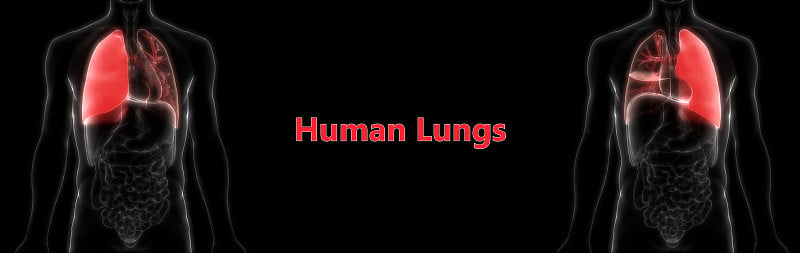

人体呼吸系统肺解剖详情

人体呼吸系统肺解剖学详情

人体呼吸系统肺解剖学详情

人体呼吸系统肺解剖详情

人体呼吸系统肺解剖详情

人体呼吸系统肺解剖详情

人体呼吸系统肺解剖学详情

人体呼吸系统肺解剖详情

人体呼吸系统肺解剖详情

人体呼吸系统肺解剖详情

人体呼吸系统肺解剖详情